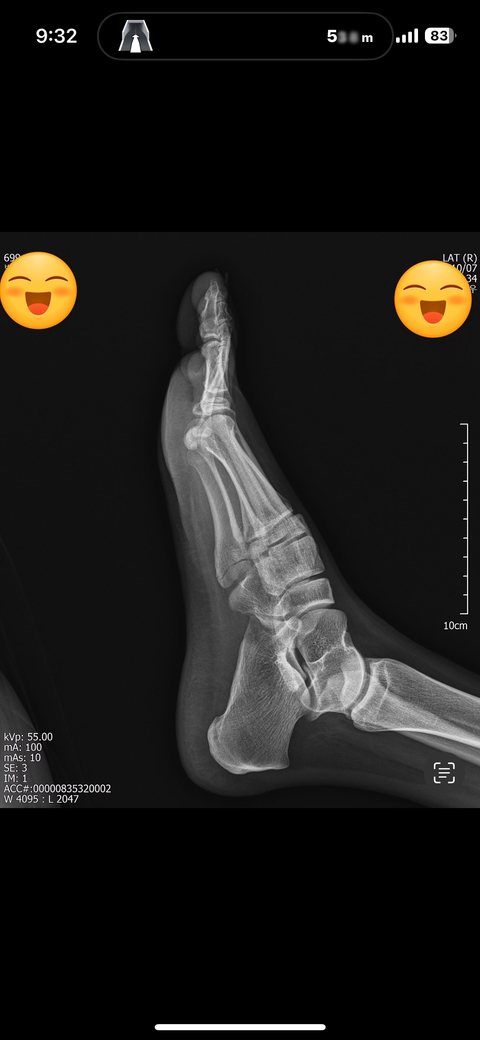

5중족골 골절 수술과비수술 봐주세요

10/5접지름으로인한 5중족골 기저부골절